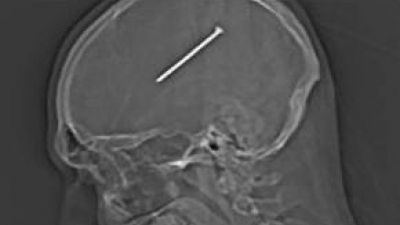

12 feb. 2014, 15:38Realitatea.NETCazul cutremurător al unui bărbat. Şi-a bătut un cui în cap şi a înghiţit o lingură